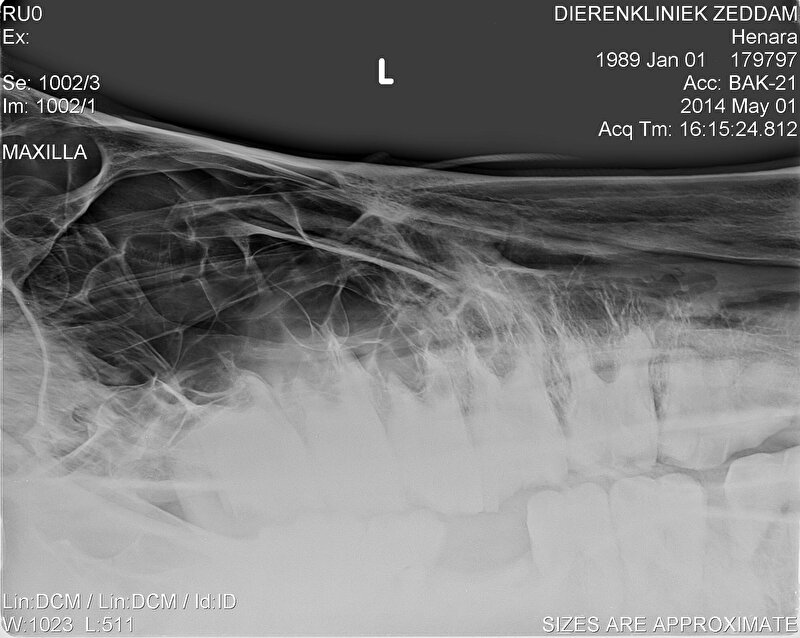

er zijn bij Hannes ondertussen al 5 1/2 kies getrokken, kan gewoon zonder verdoving. Een paard heeft niet hetzelfde gevoel als ons in de kiezen. Leuk vond ze het niet maar als je niet meer kan eten door een losse kies moet je wat...